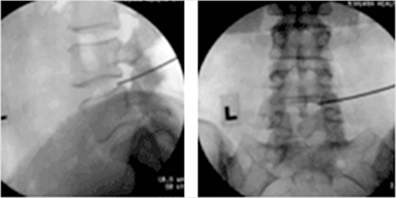

저온고주파 디스크감암술 환자 시술 사례

저온의 고수자를 이용하여 디스크에 따른 통증 해소 영상증폭장치를 통해 병변 부위를 보면서 치료 (허리디스크 적용)

▲ 저온의 고수자를 이용하여 디스크에 따른 통증 해소

▲ 영상증폭장치를 통해 병변 부위를 보면서 치료 (허리디스크 적용)